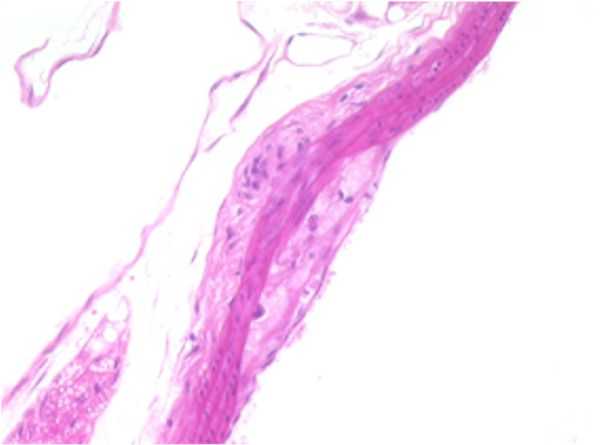

Small Artery

SMALL ARTERY: F18-01

Atherosclerotic plaque, tunica intima/media, thoracic aorta.

A focally-extensive area of the tunica media is moderately to markedly compressed by an accumulation of eosinophilic, lipoid, or fatty material within both the tunica intima and tunica adventitia.

The tunica adventitia also contains a focal, nodular, well-demarcated area of infiltrating cells characterized by mild numbers of macrophages, occasional lymphocytes, and increased collagen fibers.

The rest of the artery appears to be within normal limits. This area of constriction and corresponding proliferation may represent an area of early plaque formation.